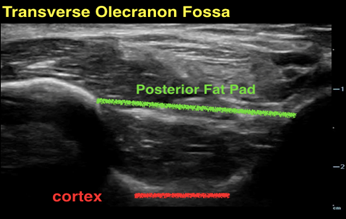

Abnormal Ultrasound

Longitudinal

In the elbow with an occult supracondylar fracture, the posterior fat pad will be elevated above

In the elbow with an occult supracondylar fracture, the posterior fat pad will be elevated above the bony prominences in both orthogonal planes